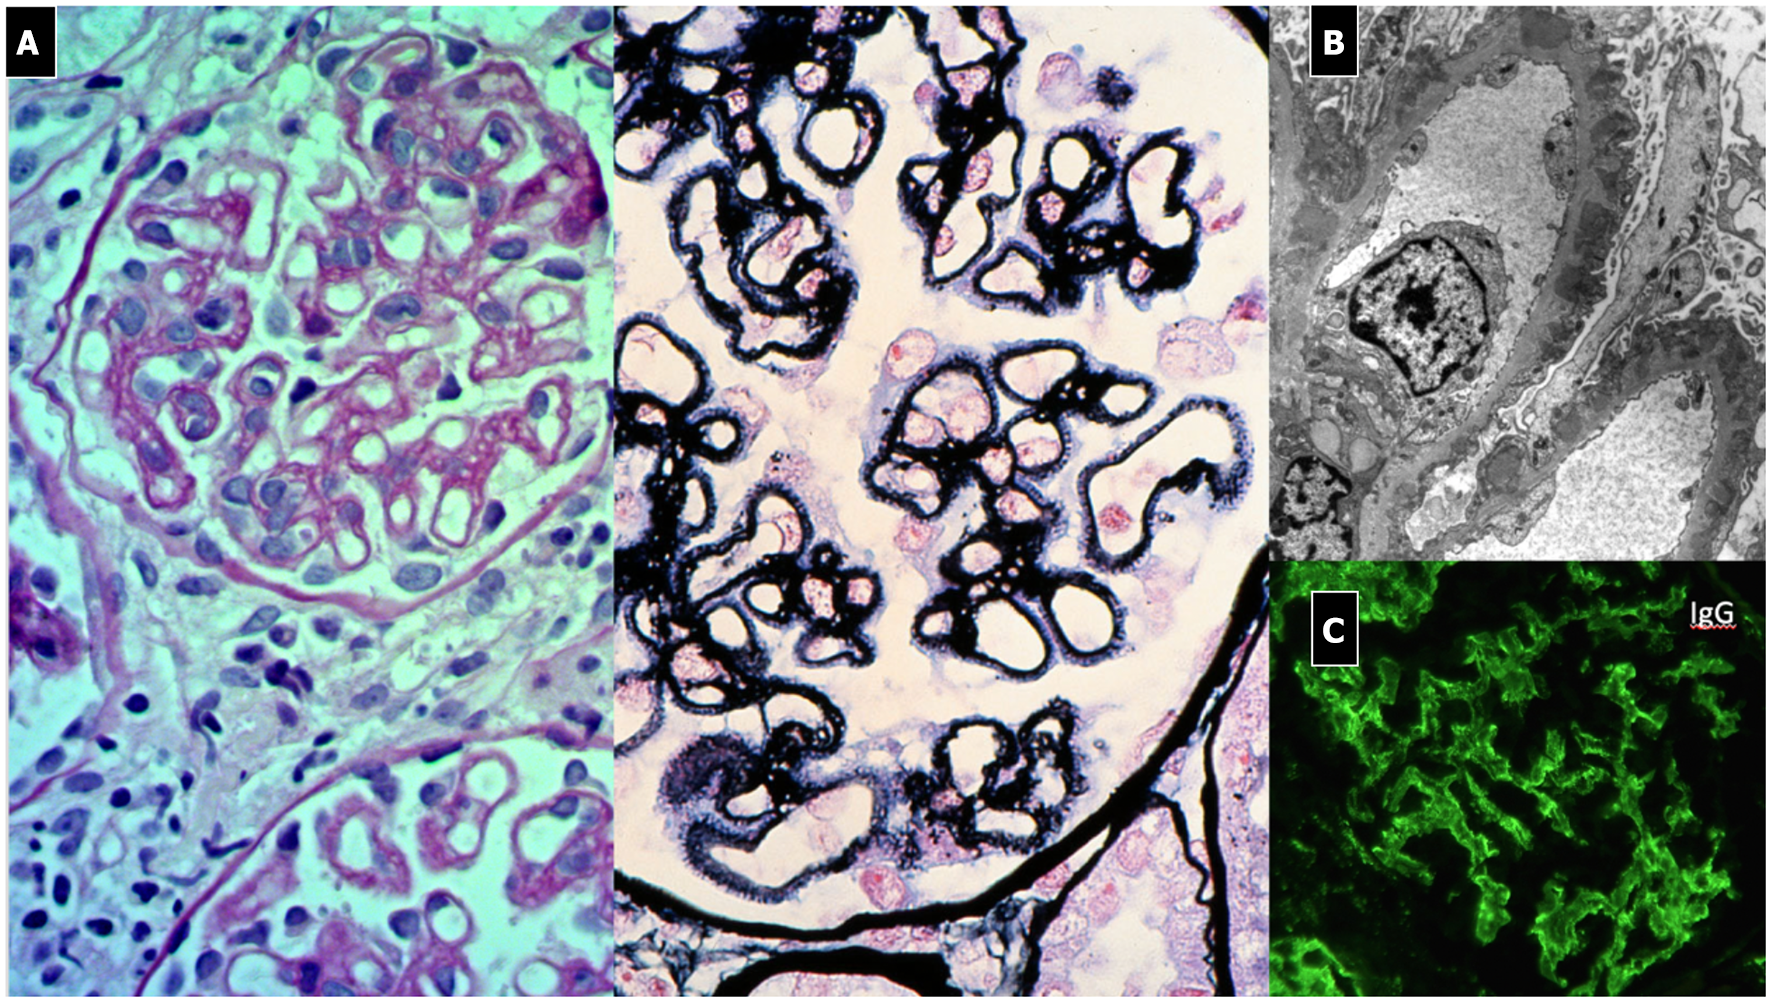

Renal Histopathology

The typical histopathological lesion is thickening of the GBM, related to the presence of immune deposits (Figure 8). During the early phases, a more rigid-appearing capillary wall may be present, with no surrounding GBM reaction (spikes). Initial immunoglobulin deposition appears like “holes” in the silver staining, as they do not stain with silver (Stage 1). As deposits persist, the GBM matrix reaction produces small spike-like protrusions (Stage 2) visualized by silver staining, followed by the matrix encircling the deposits resulting in a lace-like splitting of the GBM (Stage 3). Finally, the deposits are reabsorbed (Stage 4). Additional lesions include segmental sclerosis, interstitial fibrosis, and tubular atrophy, generally associated with a worse prognosis. Crescents are very rare and should raise the suspicion of SLE or anti-GBM nephritis. Also, the presence of mesangial deposits suggests a secondary form (Class V Lupus Nephritis). Diffuse and granular subepithelial deposits of IgG and, less frequently, C3 along the capillary wall are present on IF. Mesangial deposits are typically present in secondary forms. On EM, deposits corresponding to the stage of the disease are visualized, with a variable surrounding GBM reaction (139).

Figure 8

Membranous Nephropathy. (A) LM shows (PAS stain) regular and diffuse thickening of GBM without endothelium-mesangial proliferation and (silver stain) the GBM matrix reaction due to the presence of deposits (spikes). (B) EM shows sub-epithelial deposits with spikes of GBM that begin to encircle the deposits (Stage 1). (C) IF: diffuse and granular subepithelial deposits of IgG along the capillary wall (garland pattern).